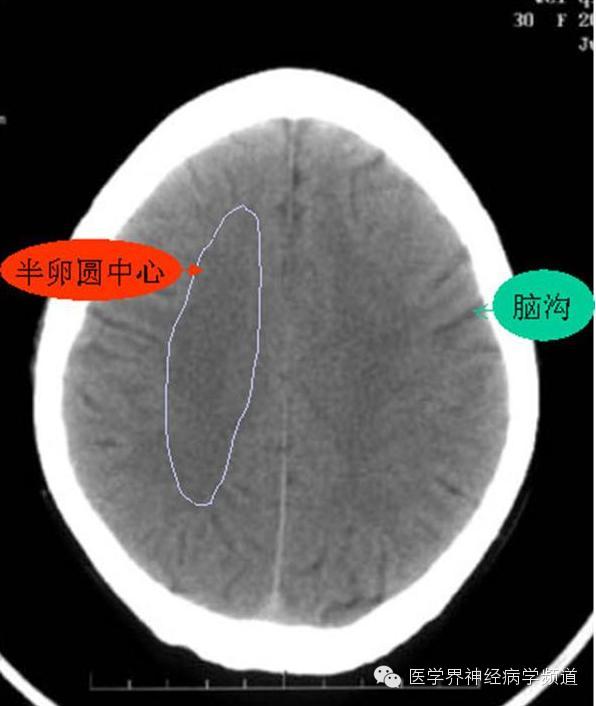

神经影像CT读片step by step